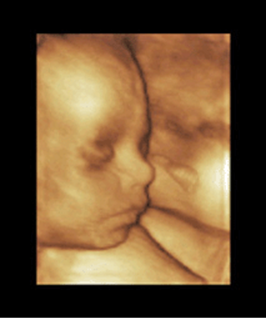

Three-dimensional sonography offers a detailed depiction of the fetal face, extremities, outer contours, and certain organs such as the fetal heart, brain, liver, kidneys, and spine (Figs. 8–4 through 8–27). Depiction of the fetus with 3D sonography has gained widespread and universal demand. However, there should be clinical indication for such studies since any unnecessary exposure to ultrasound (see the American Institute of Ultrasound in Medicine statement regarding use of 3D ultrasound for “entertainment”) should be avoided.

FIGURE 8–9. Three-dimensional sonogram of face of 20-week fetus. (Courtesy of Philips Healthcare.)